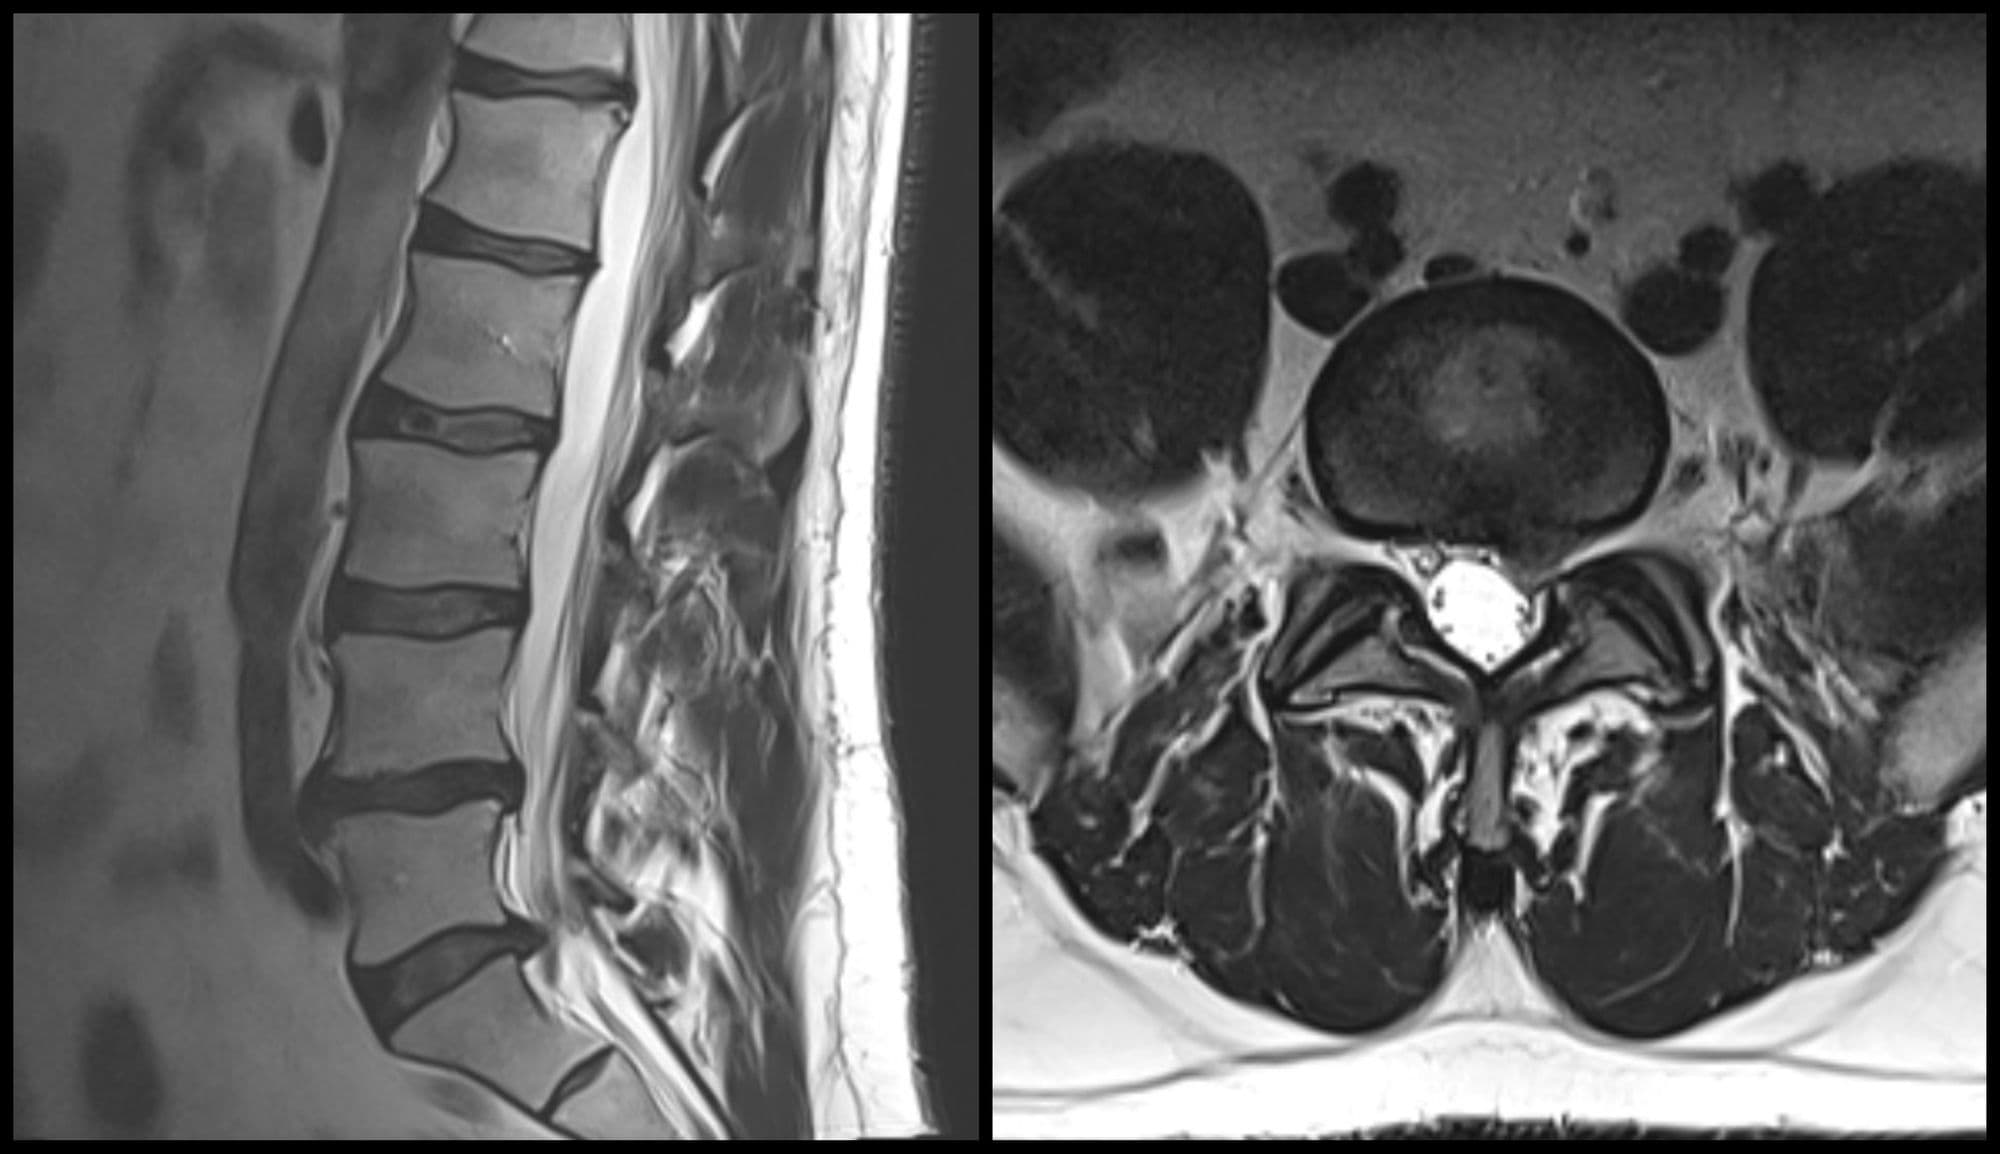

Spine

Imaging